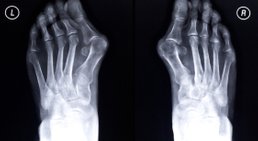

- Fußchirurgie (z.B. Hallux Valgus, Hammerzehe) und